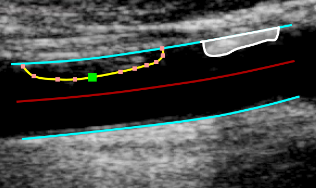

Tracing the borders

• Click the Trace the borders images/download/thumbnails/388694064/cvs_borders_button-version-1-modificationdate-1761815630116-api-v2.png button in the Setup panel.

• Start tracing the first border by clicking on the image.

• Move the mouse and click to add points to the borders.

• Right click to end the tracing of the first border.

• Start tracing the second border by clicking on the image.

• Right click to end the tracing of the second border.

Editing the borders

• Hover on the border to be modified.

• Click and drag one of the points of the border.